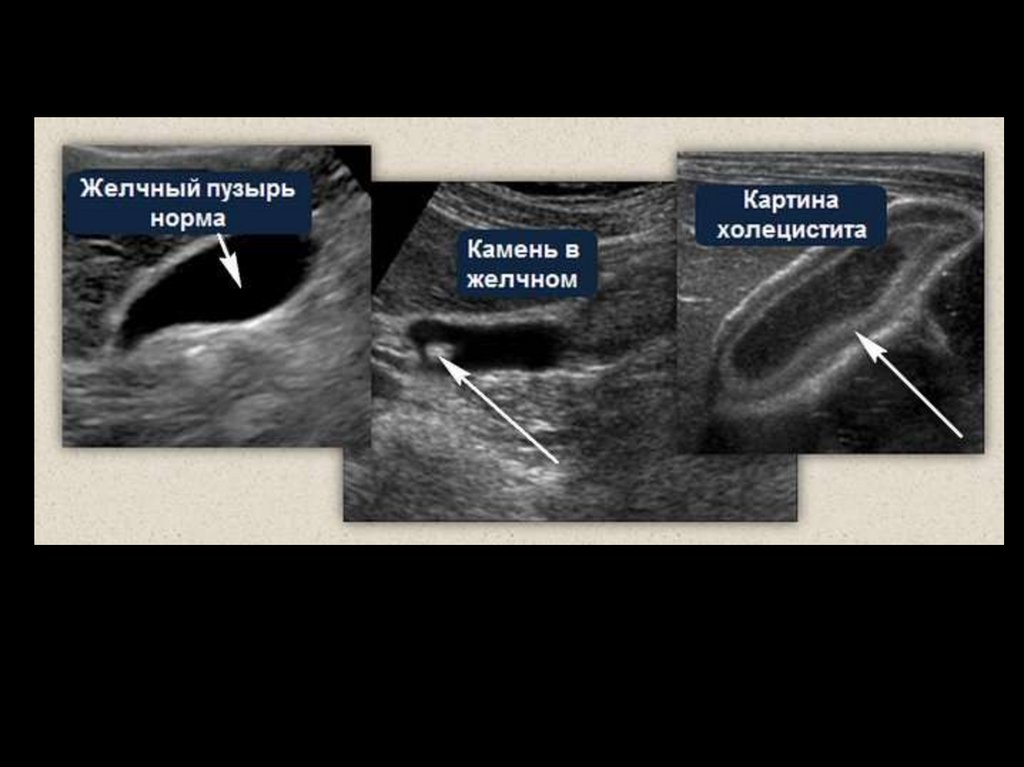

УЛЬТРАЗВУКОВАЯ КАРТИНА КОНКРЕМЕНТОВ В ЖЕЛЧНОМ ПУЗЫРЕ

132. УЛЬТРАЗВУКОВАЯ КАРТИНА КОНКРЕМЕНТОВ В ЖЕЛЧНОМ ПУЗЫРЕ